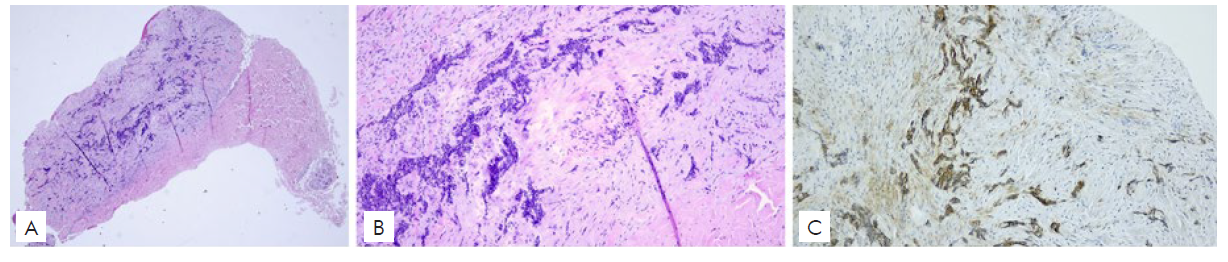

Subsequently, an incisional biopsy of a new centimetric nodular cutaneous lesion in the right arm revealed an infiltrative BCC metastasis (Fig.s 2a-b). The immunohistochemical staining showed that tumor cells were positive for CK5/6, p63, Ber-EP4 (Fig. 2c), and negative for CK20, thus supporting the diagnosis.

Figura 2 Histological images of the cutaneous BCC metastasis (Haematoxylin and Eosin) 100x (a), 400x (b), demonstrating typical basaloid morphology, and immunohistochemistry for Ber-EP4 with intense positivity of the neoplastic cells (c).